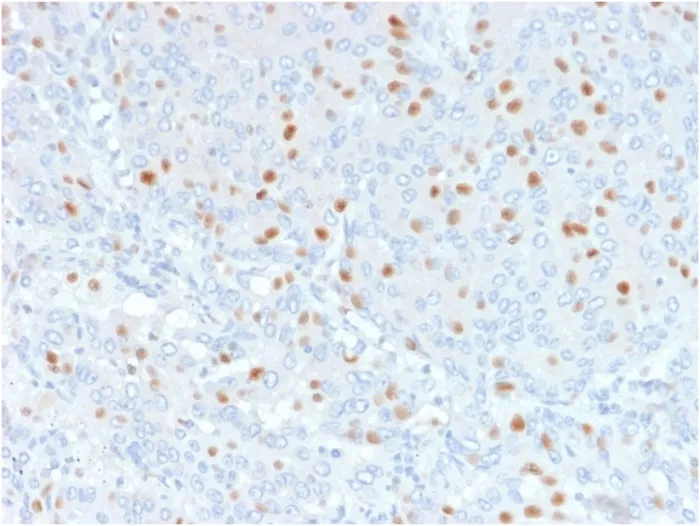

- Description: Annexin A1 belongs to the annexin family. It plays a role in glucocorticoid-mediated down-regulation of the early phase of the inflammatory response. In resting conditions Annexin A1 is localized to the cytoplasm. Upon activation it is mobilized to the membrane and secreted. Annexin A1 and contains 4 annexin repeats. A pair of annexin repeats may form one binding site for calcium and a phospholipid. Expression of the ANXA1 gene is upregulated in hairy cell leukemia (HCL). Detection of ANXA1 provides a simple, highly sensitive and specific assay for diagnosing HCL. Annexin A1 has also been found to be protective against DNA damage induced by heat in breast cancer cells, suggesting it is involved in tumor suppressive and protective activities, and also is associated with treatment resistance. Primary antibodies are available purified, or with a selection of fluorescent CF® Dyes and other labels. CF® Dyes offer exceptional brightness and photostability. Note: Conjugates of blue fluorescent dyes like CF®405S and CF®405M are not recommended for detecting low abundance targets, because blue dyes have lower fluorescence and can give higher non-specific background than other dye colors.

- Applications: Flow, intracellular (verified) | IHC, FFPE (verified)

- Validated Applications: FC, IHC, FFPE

- Positive Control: HeLa, A431, K562 cells; human esophagus, placenta and prostate tissues.